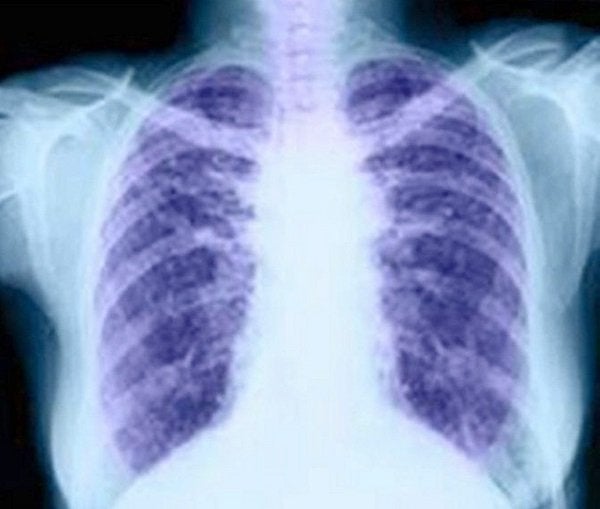

Un nuevo sistema epigenético permite el diagnóstico precoz del cáncer de pulmón

Un nuevo sistema basado en biomarcadores epigenéticos para el diagnóstico precoz de cáncer de pulmón fiable, mínimamente invasivo y asequible permite ayudar a una detección más rápida de este tipo de tumor y, con ello, reducir las elevadas tasas de mortalidad actuales.